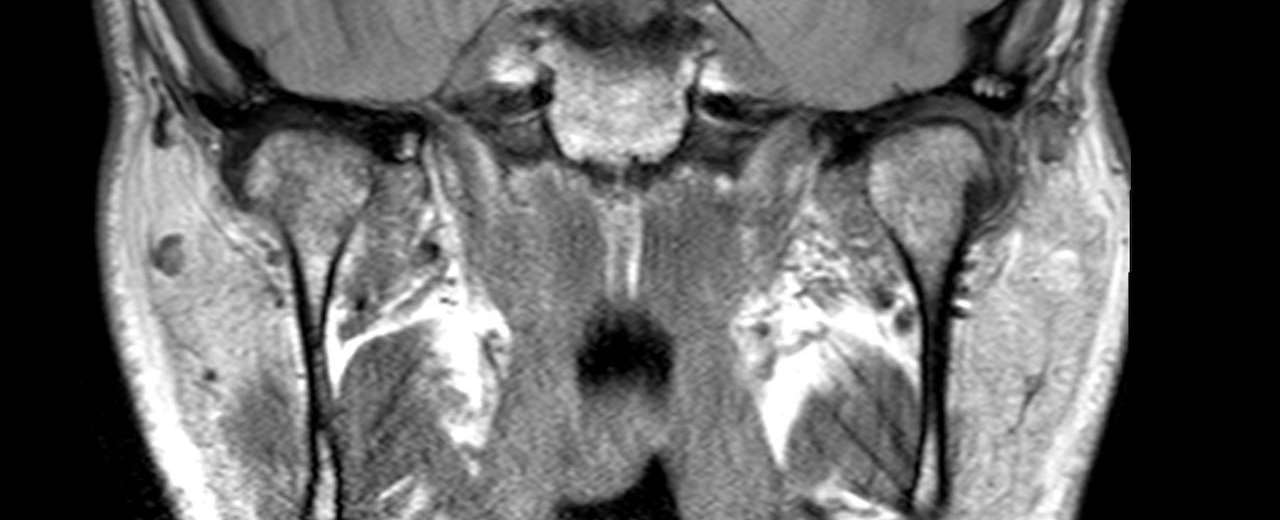

MRI imagine assists in our TMJ/D diagnosis

3-D MRI soft tissue imaging is used in Dr. Nick Yiannios’ practice to assist in TMJ/D diagnostics, and also to help vet a patients TMJs in cases where large restorative treatment plans are planned, when indicated, such as before the initiation of:

After all, 2/3 of the human bite/occlusion are the orthopedic TMJs themselves; it’s not just the teeth coming together.  The joints affect the bite, via orthopedic biomechanics, and the TMJ cartilage, if damaged, often alters the bite.  This may or may not be problematic, but an MRI will typically tell Dr.Nick if indeed the former or the latter situation exists for a given patient.

Few dentists actually understand how to objectively vet the TMJs, and the TMJ MRI data combined with TMJ CBCT data is literally the gold standard in TMJ diagnostics, and ultimately occlusal/bite diagnostics.  Dr. Nick’s CNO teaching center trains other dentists how to order, interpret, and implement diagnostic information about the TMJs gleaned from both TMJ CBCT and MRI. Local medical imaging centers and radiologists work with Dr. Nick to implement his TMJ MRI prescriptions, and a medical radiologist also inspects all of the MRI scans that the practice orders, looking for other medical pathologies that might be found within the scans.